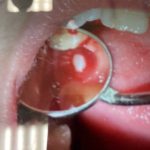

赤い歯⁉️

本日もたくさんのご予約ありがとうございます。赤い歯を見て、皆様驚きましたか^_^

いえいえ😆これは制作過程の、ひとつです。

お客様の歯型を取らせて頂きお客様の理想とする歯のかたちへ近づけるためのイメージを担当医がしているものです💕

歯の形や並び方、出っ張りかたなど気にされていることがありましたらどうぞご相談ください